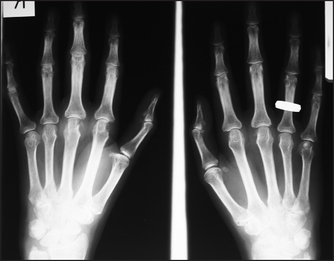

It is not usually necessary to X-ray all symptomatic joints; information about joint destruction and typical changes that help make the diagnosis can be obtained from selected X-rays. For example, a clinical presentation with a polyarthritis may warrant hand and foot X-rays which, if they show erosion and a typical pattern (e.g. metatarsophalangeal and metacarpophalangeal involvement), can help make the diagnosis of rheumatoid arthritis (see Figures 26.6 and 26.7).

Figure 26.6 Rheumatoid arthritis, early findings X-ray of the hands of a patient with early rheumatoid arthritis. Note erosions of the heads of the metacarpophalangeal joints and of the ulnar styloid, and reduced amounts of cartilage in the joint spaces.